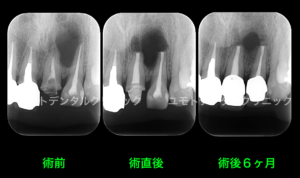

以下のような透過像が比較的大きなケースにおいて症状の早期の軽減、消失を考えた際に、抜歯を行い、病気を解決させるというお話も選択肢には上がってくるやもしれません。

重度のPや重度のう蝕と違い、根尖性歯周炎の解決作が抜歯という選択肢だけではないのはご承知いただいている上で、加えて根尖の透過像の大きさも歯内療法の成功の成否には関わり合いがないことをご承知いただければと思います。

(大きな根尖病変は小さな根尖病変に比べ、治療後に縮小傾向を示し完全なる骨再生、ないしは瘢痕治癒を確認できるまでの期間が長いことは報告されております)

本症例においては透過像の原因歯は左上1番と診断しておりますが、左上2番の症状も該当歯とは別に確認されたため、左上1番の再根管治療後に両歯を外科的歯内療法を行っております。

根管治療前、外科的歯内療法直後、術後6ヶ月

本ケースにおいては唇側から口蓋側に交通する骨欠損を生じていたため、骨の完全な再生ではなく瘢痕治癒という形態を最終的なゴールと定めさせていただきました。

治療を受けていただくだけでなく、治療後の予後観察(検診)は非常に大切です。